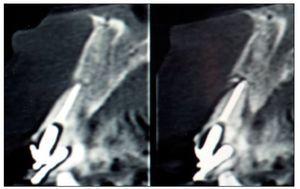

Figura 6. Tomografía computarizada de control realizada a los 6 meses.

Figura 11. Tomografía computarizada de control realizada a los 6 meses.

El implante (Superline, Dentium o Tapered Screw-Vent, Zimmer) fue instalado a los 6 meses de realizado el procedimiento de aumento tisular, previa realización de una tomografía computarizada para controlar la ganancia ósea. En 4 pacientes se realizó una técnica sin colgajo, y en los 4 casos restantes se realizó un colgajo mínimamente invasivo.